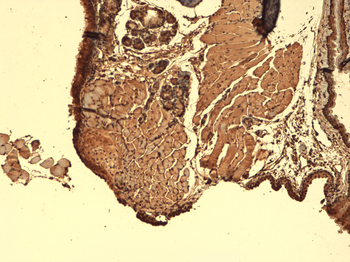

IHC-P image of human thyroid cancer tissue using NIS antibody (2.5 ug/ml)